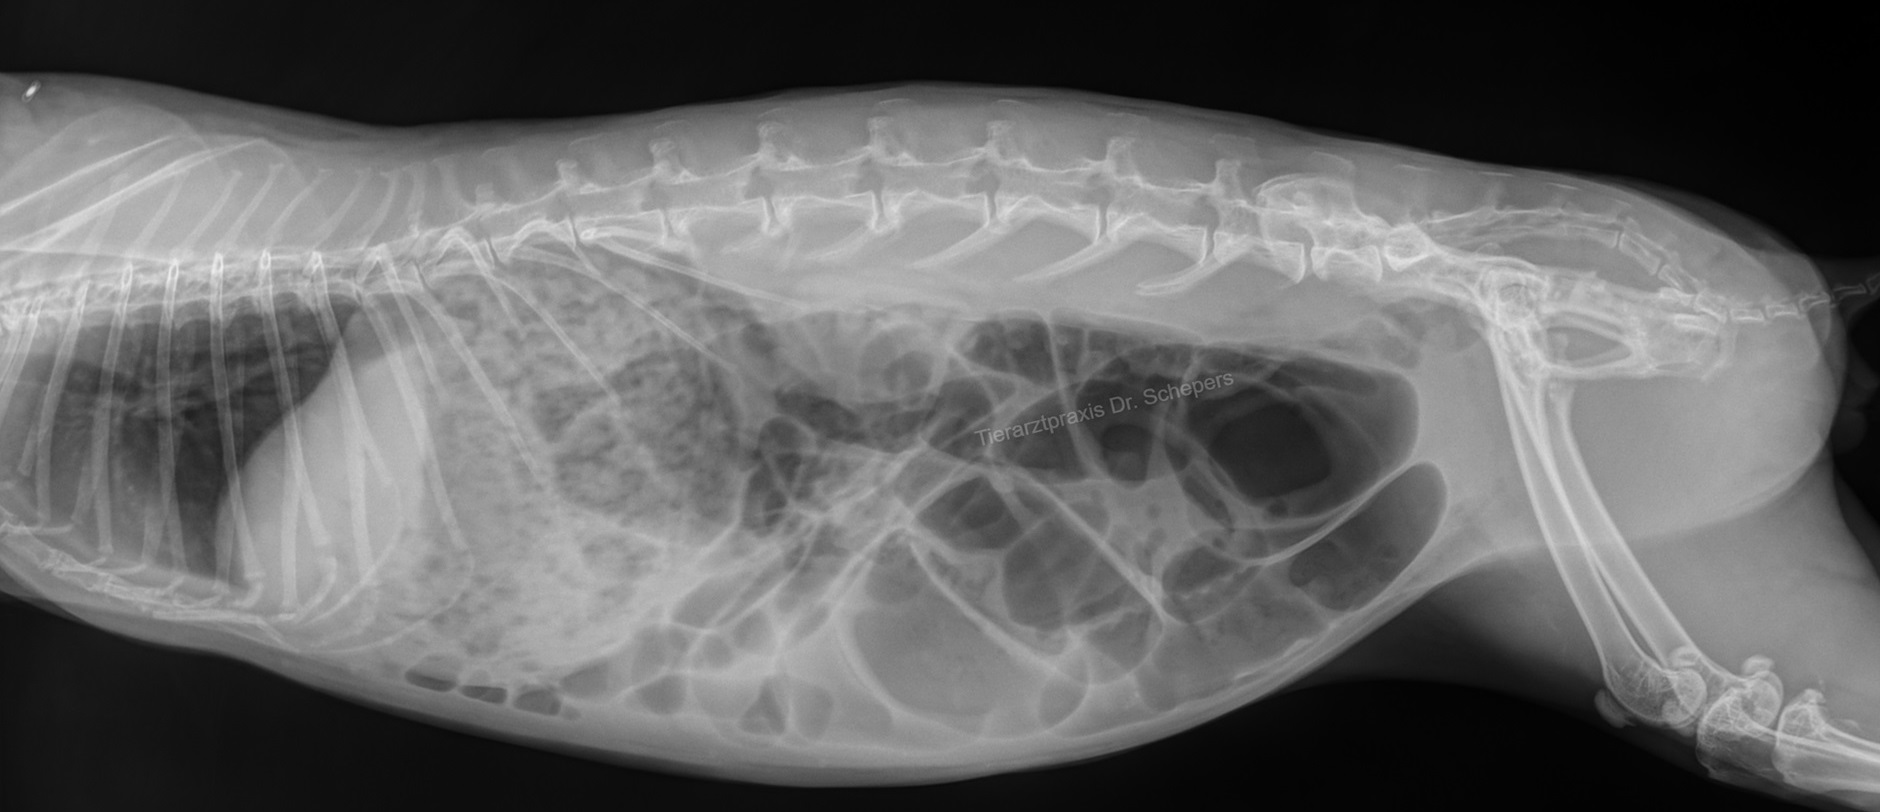

Röntgenuntersuchung

Die Röntgenuntersuchung ist mitunter überlebenswichtig, um einen Darmverschluss rechtzeitig zu erkennen! Erst, nachdem ein solcher ausgeschlossen wurde, darf bzw. muss ein aufgegastes Kaninchen engmaschig zwangsgefüttert werden, damit das Gas zügig aus dem Darm "geschoben" wird und die Symptome abklingen können.

Ein Kaninchen mit einem massiv vergrößerten Magen und / oder einem Darmverschluss hingegen darf keinesfalls zwangsgefüttert werden! Hier muss zunächst die ursächliche Verstopfung behoben werden - dann entleert sich der überdehnte, unter Druck stehende Magen von selber in den Darm.

Es kann durchaus 2-3 Tage dauern, bis eine Besserung eintritt und die Tiere außer Lebensgefahr sind. Auch danach vergehen mehrere Tage, bis das komplette Gas ausgeschieden wurde. Oft sind röntgenologisch und palpatorisch (=  beim Tasten) noch riesige Gasmengen feststellbar, wenn das Allgemeinbefinden bereits besser und der Kreislauf wieder stabil ist. Die Medikation muss dann unbedingt konsequent fortgeführt werden, auch wenn eine intravenöse Verabreichung und Infusion nicht mehr erforderlich sind.